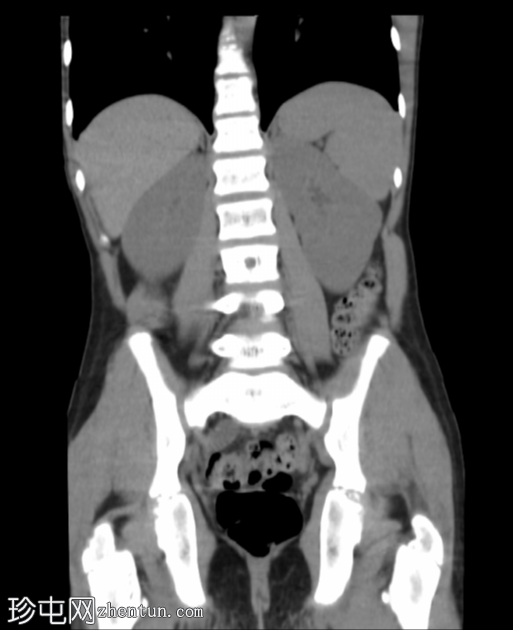

冠状位

平扫

腹部和盆腔CT扫描结果正常。

泌尿系统正常。未见尿路结石或反流压改变。

本病例显示一名10岁男孩的腹部、盆腔和泌尿系统CT扫描结果正常。